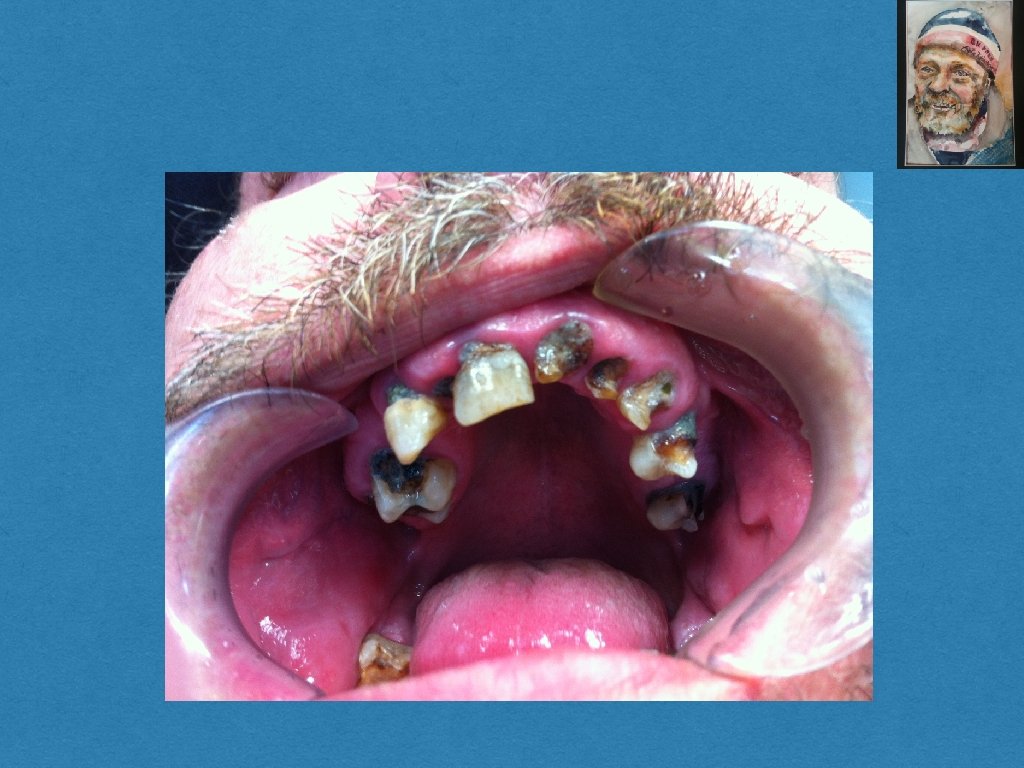

Socialt udsatte